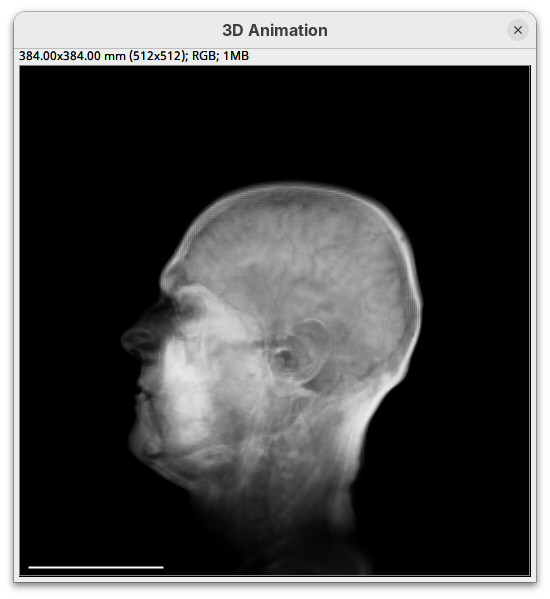

3D Viewer

The 3D Viewer (Schmid et al. 2010) is a 3D visualization plugin bundled in Fiji. It has been the default 3D rendering engine for many years and provides a good starting point for visualizing and interacting with 3D images. The interface provides some rendering and animation options, but it is possible to create more advanced visualizations and animations with code. For more details, please consult the documentation.

Here, we’ll only open our dataset with 3D Viewer for visualization.

- Go to

Plugins>3D Viewer.

An import dialog will open. In addition to the image field itself, pay attention to the Resampling factor parameter. The default is 2, which means 2x downsampling of the original stack. Always downsample at least 2x because 3D Viewer will crash when trying to open large datasets.

- Click

OKon the options dialog and when asked about converting to 8-bit.

The main interface will open.

- Explore the sample interactively.